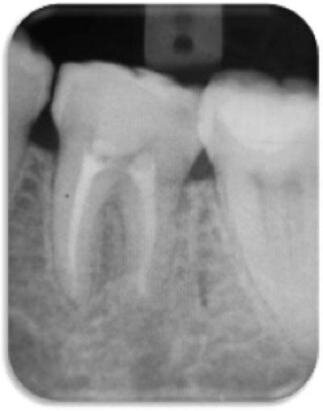

Po opracowaniu przeprowadzono usuwanie warstwy mazistej i dezynfekcję systemu kanałów korzeniowych laserem Er,Cr:YSGG z końcówkami RFT.32,33 Naświetlanie laserem prowadzono z użyciem końcówki 200 μm (RFT2, Biolase; współczynnik kalibracji 0,55) o ustawieniach na panelu: 0,75 W (energia impulsu 37,5 mJ), częstotliwości impulsów 20 Hz, czasie trwania impulsu 140 μs, 0% wody i 0% powietrza. Końcówkę umieszczono na głębokości 1 mm przed końcem WL i przeprowadzono napromieniowanie z prędkością ok. 2 mm·s-1, cofając się w kierunku korony (Ryc. 3). Procedurę napromieniowania powtarzano 4 razy: 2 razy z kanałem wypełnionym wodą destylowaną, a następnie 2 razy w warunkach suchych, z 15-sekundową przerwą pomiędzy poszczególnymi naświetleniami. Otwór dostępowy pozostawiono wypełniony sterylnym wacikiem i zamknięto opatrunkiem tymczasowym (IRM, Dentsply).

Podczas drugiej wizyty (po 1 tygodniu) pacjent nie zgłaszał bólu, tkliwości opukowej lub opuchlizny. Po wyizolowaniu pola koferdamem kauczukowym kanały ponownie wypełniono wodą destylowaną i przeprowadzono napromieniowanie laserowe z użyciem końcówki 320 μm (RFT3, Biolase, USA; współczynnik kalibracji 0,85) o ustawieniach na panelu: 1,25 W (energia impulsu 62,5 mJ), częstotliwość impulsu 20 Hz, czas trwania impulsu 140 μs oraz 0% wody i powietrza. Cykle naświetlania i powtórzenia były identyczne, jak podczas pierwszej wizyty.